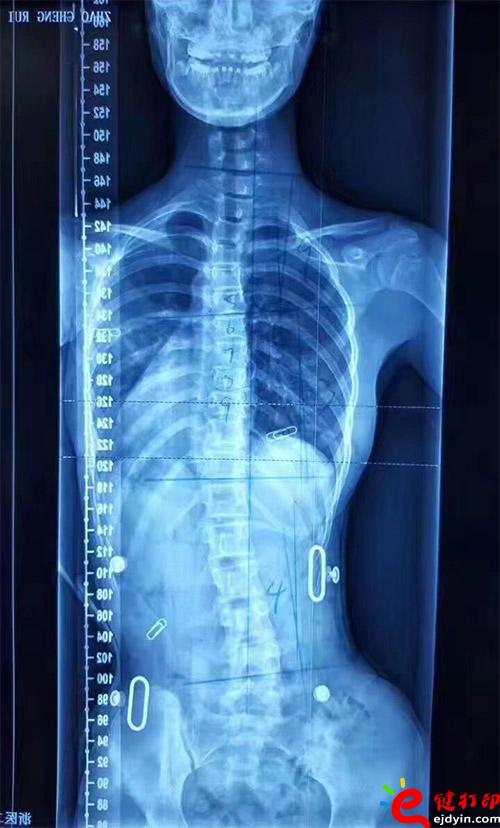

3D打印矯形器

不多說,直接上案例就知道了。這是真實案例。

在脊柱側彎患者中,僅有10%的青少年特發(fā)性脊柱側彎患者最終需要手術治療,90%的患者可以保守治療和積極觀察。非手術治療中公認最主要和可靠的方式是用矯形支具治療。像上圖這樣的案例就可以通過矯形器治療。每個人的畸形不一樣,就需要像3D打印這樣可定制又便宜的技術幫助。